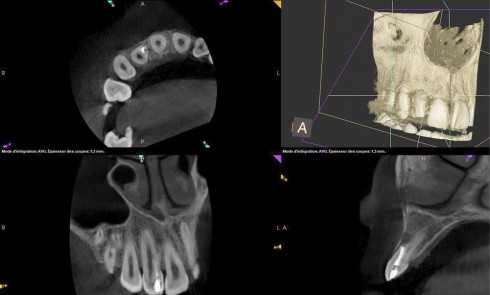

Grand Prix éditorial ID 2023, L’implantologie numérique, maintenant et demain 3e cas lauréat 2023 Présentation du cas Un patient se...

Article réservé à nos abonnés Apport du numérique dans la gestion d’une arcade édentée en bridge implanto-porté type « FP1 »